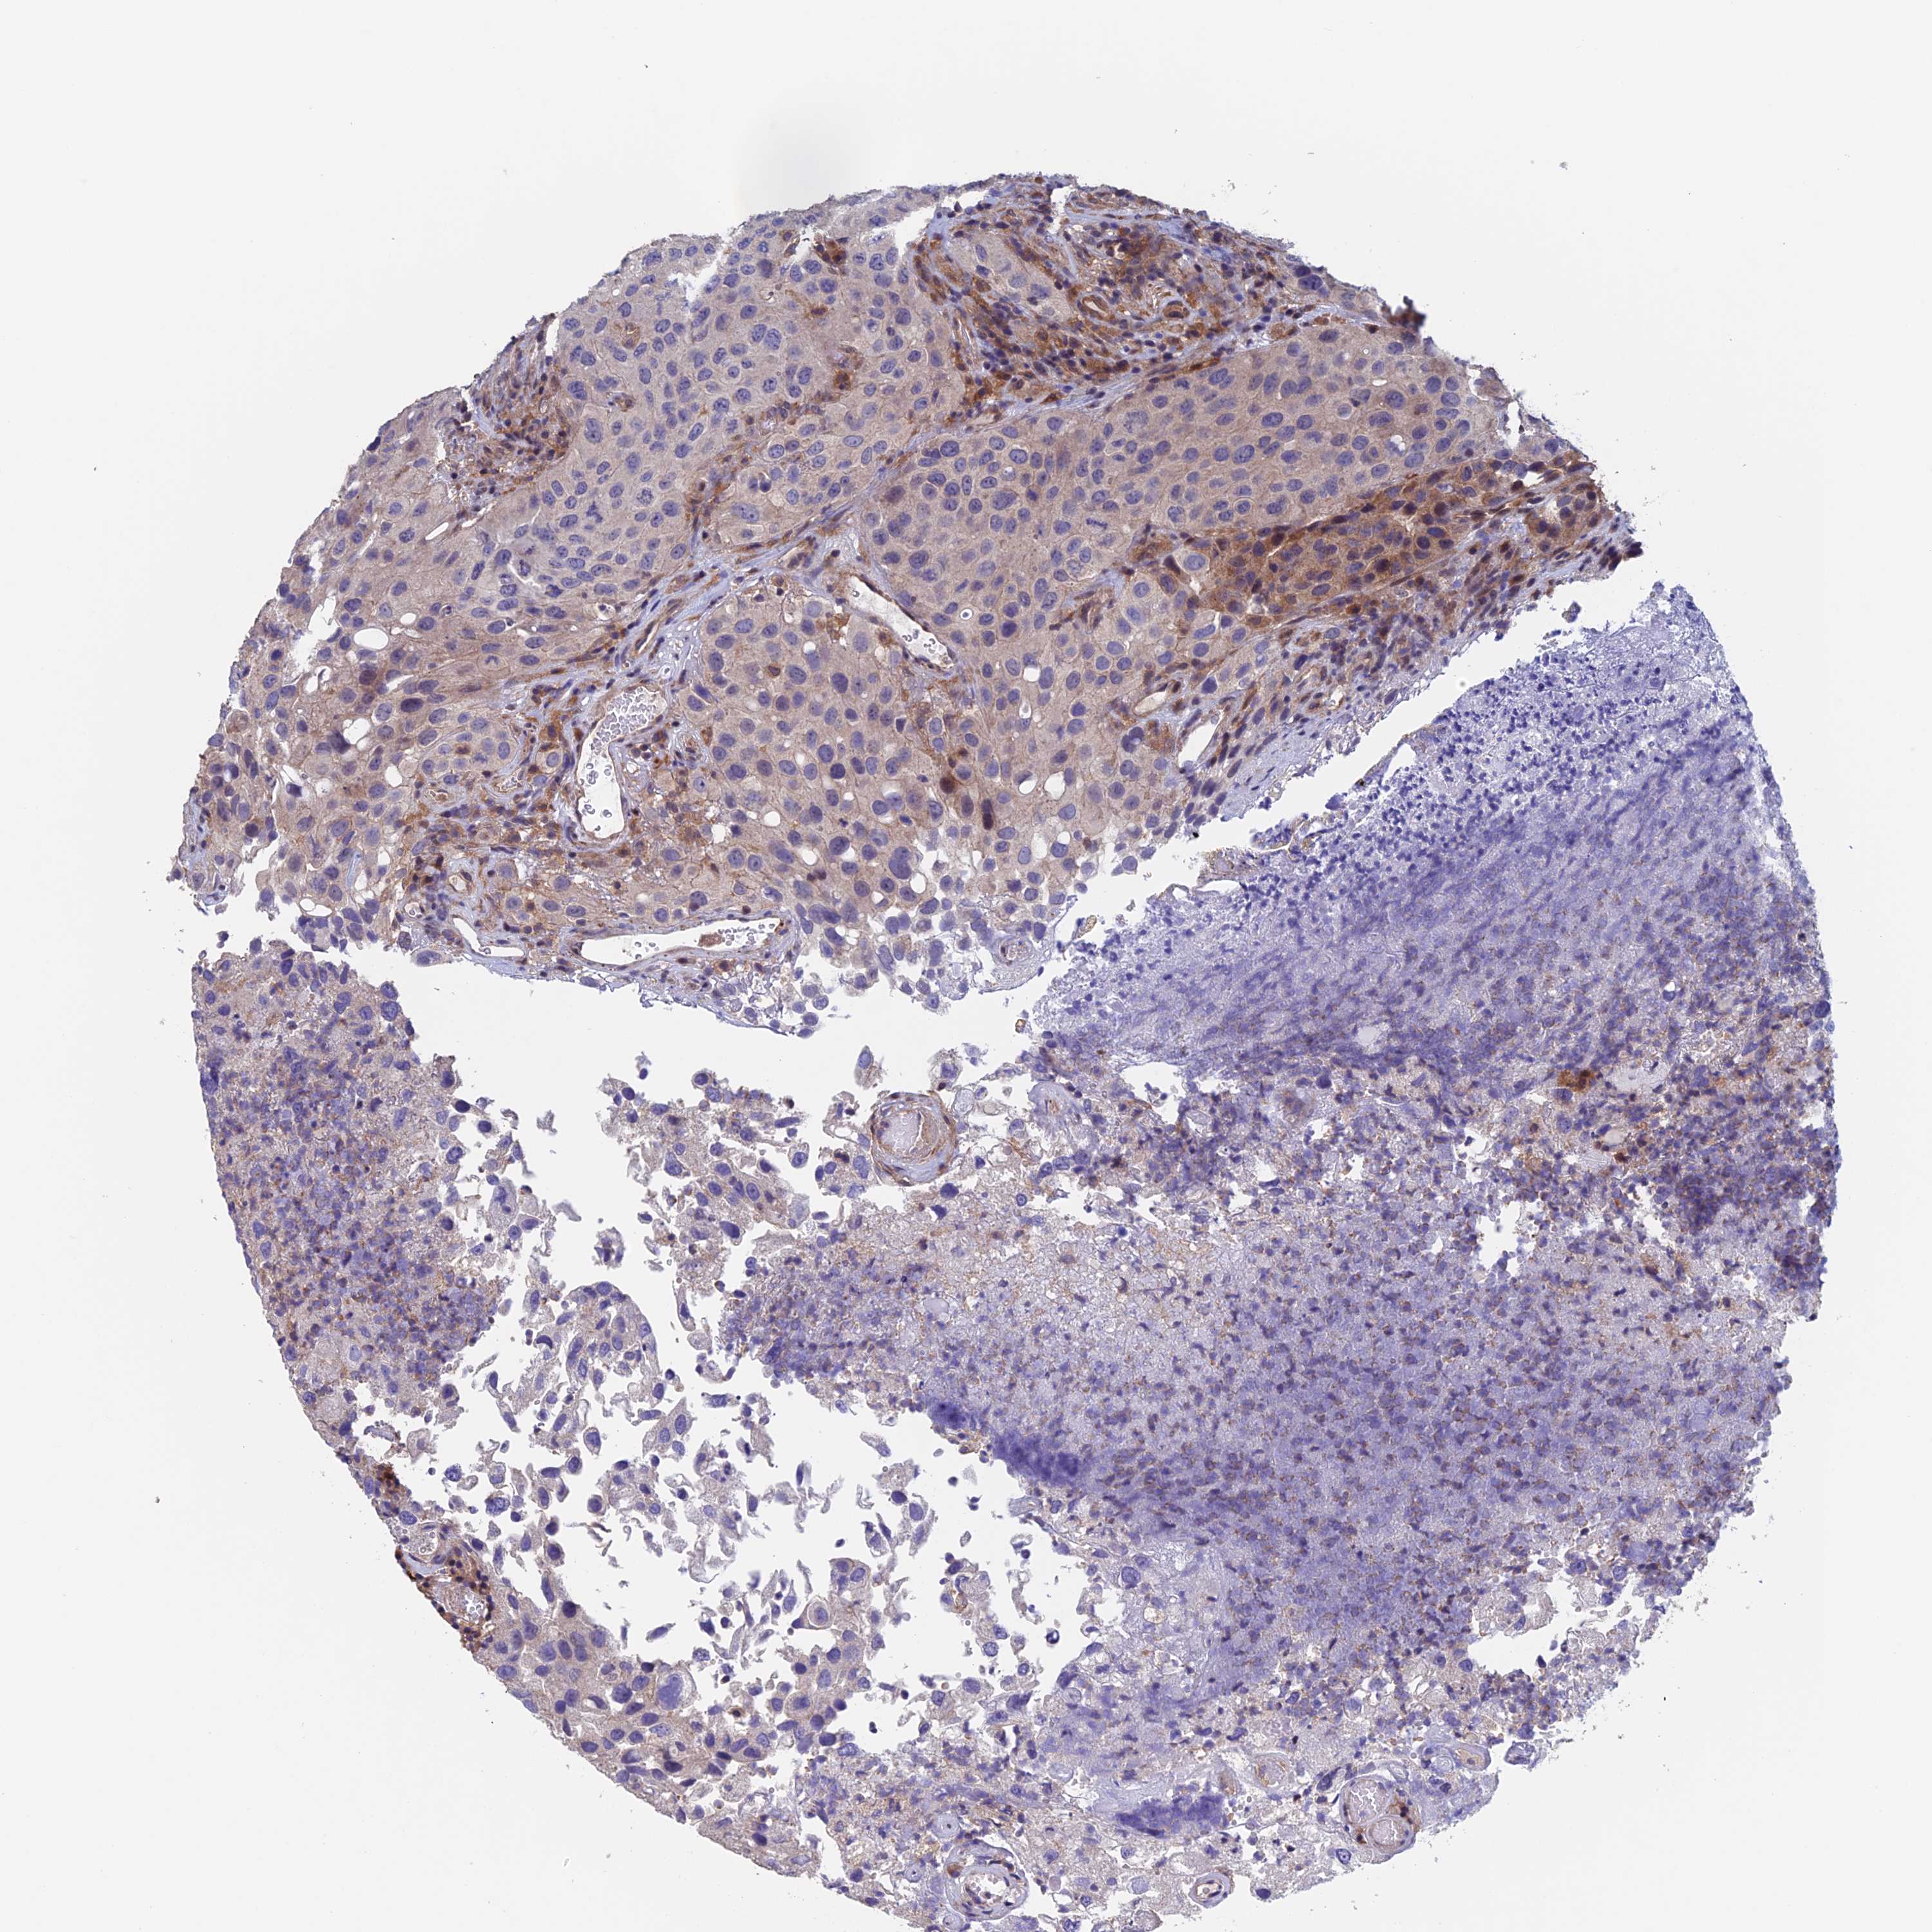

UROTHELIAL CANCER - Protein expressioni

A mouse-over function shows sample information and annotation data. Click on an image to view it in a full screen mode. Samples can be filtered based on level of antibody staining by selecting one or several of the following categories: high, medium, low and not detected. The assay and annotation is described here.

Antibody stainingi

Antibody staining in the annotated cell types in the current human tissue is reported as not detected, low, medium, or high, based on conventional immunohistochemistry profiling in selected tissues. This score is based on the combination of the staining intensity and fraction of stained cells.

Each image is clickable and will lead to virtual microscopy that enables deeper exploration of all samples and also displays staining intensity scores, fraction scores and subcellular localization as well as patient and tissue information for each sample.

Antibody HPA044186

Antibody HPA063605

Urothelial carcinoma, High grade

Urothelial carcinoma, Low grade

Urothelial carcinoma, NOS